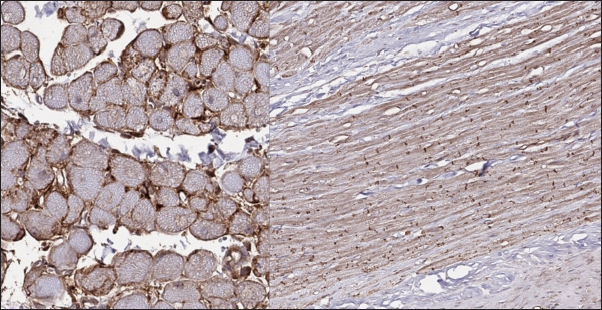

Fig. 4. Immunohistochemistry. Normal myocardium of the cat. Cx43 proteins located in zones of cell-to-cell contact. Stained with Cx43 antibodies.

In the myocardial samples of healthy cats, we did not find any significant structural alterations. The cardiomyocytes were presented as cell stripes with one or two centrally located nuclei, Z disks were easily recognized, and striation was presented. The interstitial spaces were not expanded, and the capillary lumen was noticed. Masson’s trichrome staining for fibrosis did not reveal a significant increase in collagen fibers, with sporadic fibers observed in interstitial spaces and near vessels (Fig. 3). Immunohistochemical staining for Cx43 revealed the typical distribution of proteins accumulated in cell-to-cell connections via intercalated disks. Weak-to-absent signals were observed in the lateral wall of the cardiomyocytes. The immunoadsorption zone exhibited a solid line without disruptions or lesions (Fig. 4).